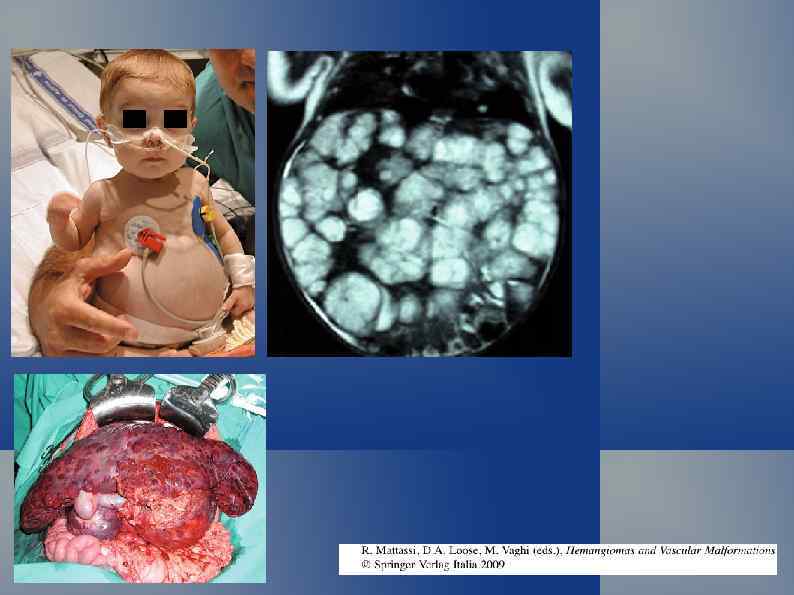

Диссеменированный гемангиоматоз новорожденного